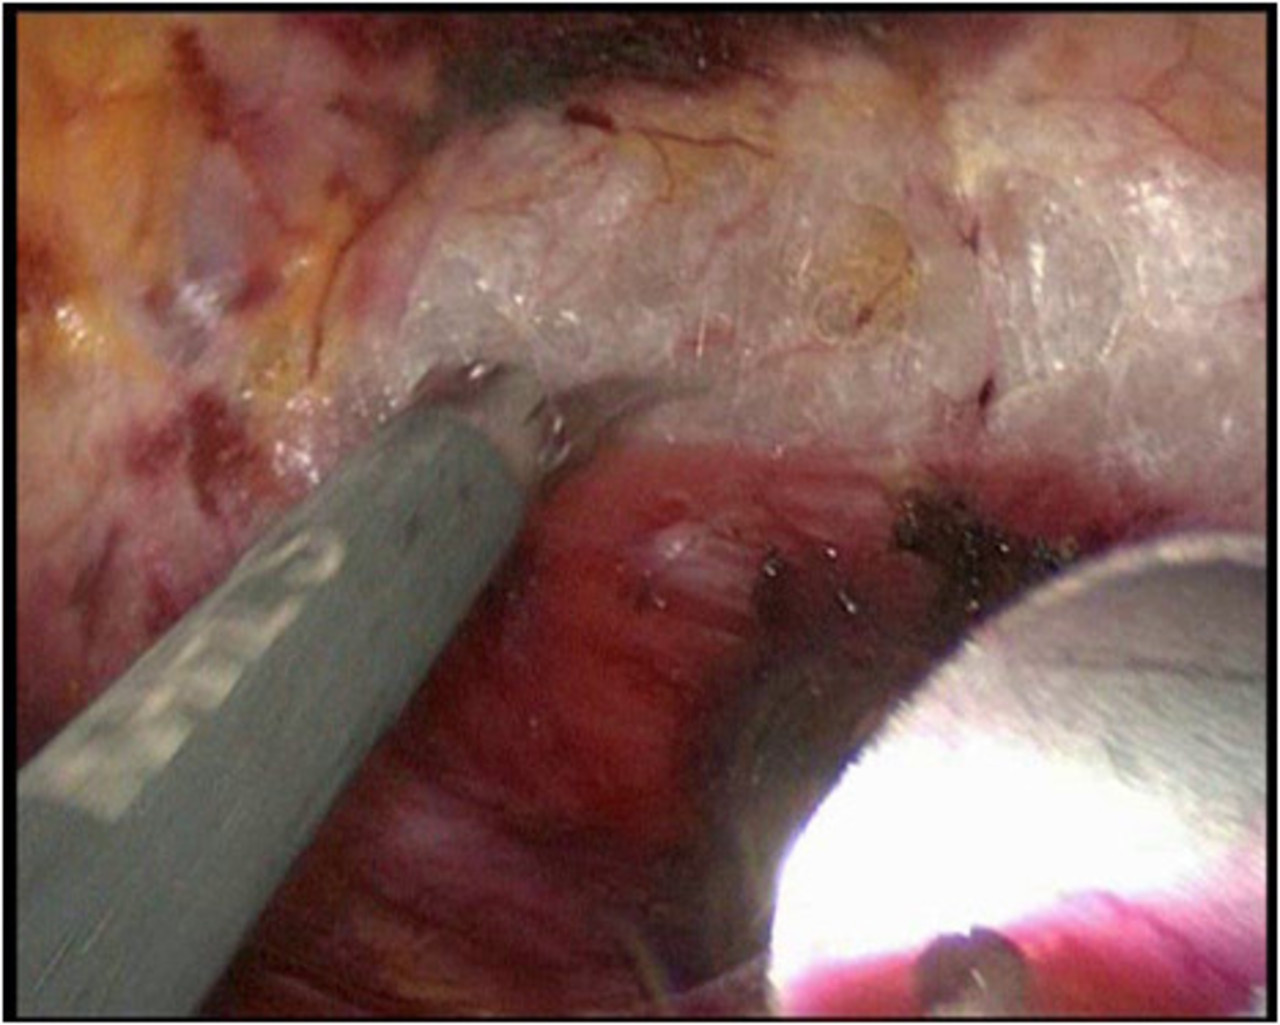

Wir führen neben der konventionellen Schnittoperation seit Jahren auch als eine der wenigen Kliniken in Deutschland die minimal invasive Schilddrüsenresektion nach der „ABBA-Methode“ durch. Welche Operationsmethode im Einzelfalle eingesetzt werden kann hängt von der Schilddrüsenerkrankung und der Größe ab und wird im Vorfeld mit dem Patienten ausführlich abgewogen und besprochen.

Minimal invasive Schilddrüsenoperation (ABBA):

Bei der von uns durchgeführten minimal invasiven Schilddrüsenoperationstechnik handelt es sich um die sog. „ABBA-Technik“ (Axillo-bilateral-breast-approach). Dabei wird die Schilddrüse durch einen ca. 2 cm langen Hautschnitt im Bereich der vorderen Achselhöhle sowie über 2 winzige Schnitte im Bereich der Brust (Randbereich der Brustwarze) operiert. Bei dieser Technik erfolgt die Präparation streng im Unterhautfettgewebe – Nerven, Gefäße oder die Brustdrüse werden dabei nicht tangiert. Ähnlich wie bei minimal invasiven Bauchoperationen wird das Operationsgebiet mit CO2-Gas gefüllt, um ausreichend Raum für die Einführung der feinen Operationsinstrumente zu erreichen. Die Schilddrüse wird dann unter Kamerasicht analog der herkömmlichen Operationstechnik operiert. Die Übersicht bei dieser Operation ist hervorragend; sämtliche Nerven- und Gefäßstrukturen können genau identifiziert werden. Ebenso werden die Stimmbandnerven mittels Neuromonitoring kontrolliert und die Nebenschilddrüsenkörperchen dargestellt und geschont.